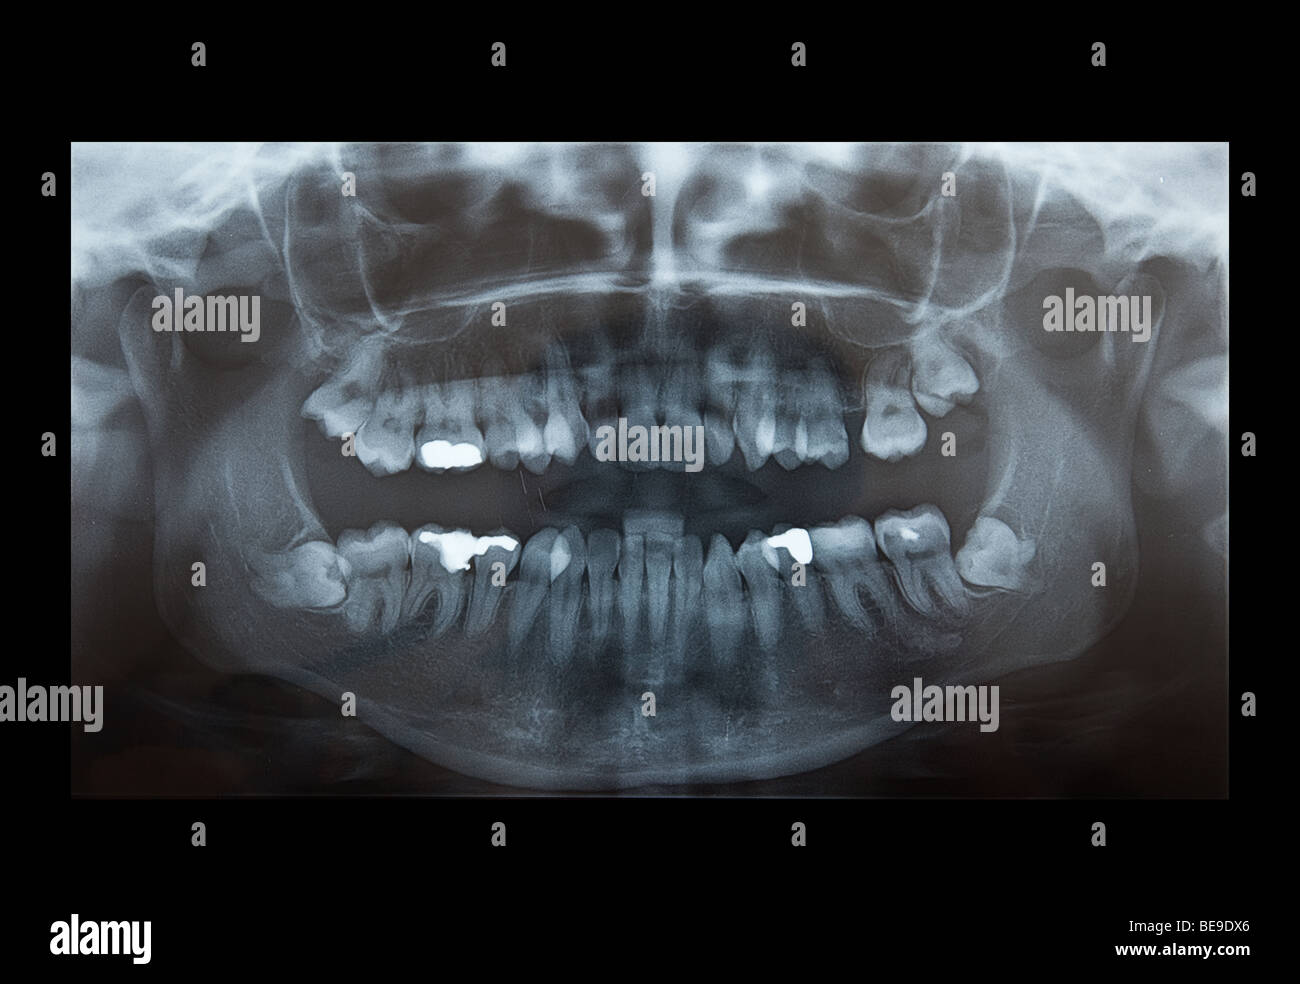

Panoramic X-ray Image Of Teeth And Mouth With Wisdom Teeth | Parkview

fountainhillsdentist.comwisdom teeth ray mouth panoramic back tooth

fountainhillsdentist.comwisdom teeth ray mouth panoramic back tooth